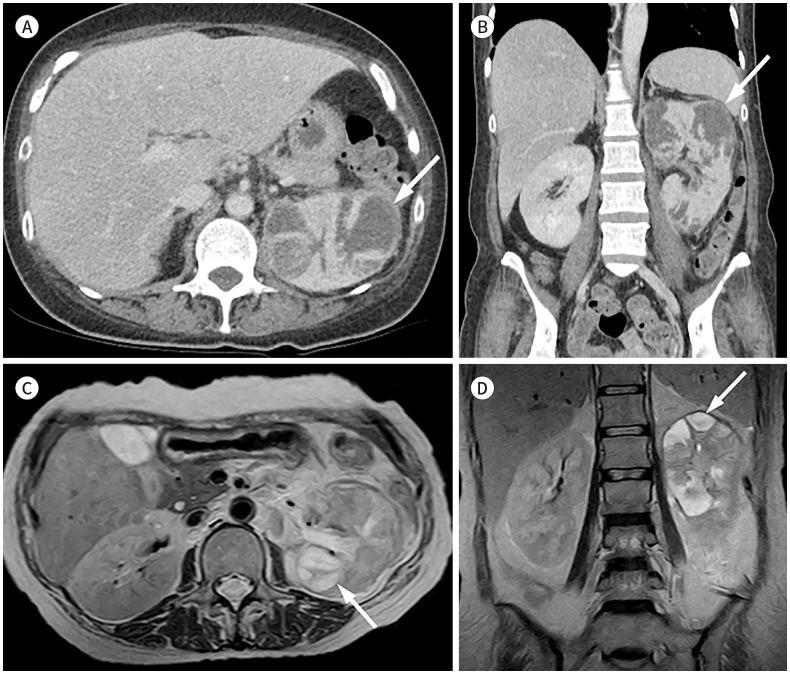

Xanthogranulomatous (XG) inflammatory disease is a rare benign disease involving various organs, including the gallbladder, bile duct, pancreas, spleen, stomach, small bowel, colon, appendix, kidney, adrenal gland, urachus, urinary bladder, retroperitoneum, and female genital organs. The imaging features of XG inflammatory disease are nonspecific, usually presenting as a heterogeneous solid or cystic mass. The disease may also extend to adjacent structures. Due to its aggressive nature, it is occasionally misdiagnosed as a malignant neoplasm. Herein, we review the radiological features and clinical manifestations of XG inflammatory diseases in various organs of the abdomen and pelvis.

黄色肉芽肿性(XG)炎性疾病是一种罕见的良性疾病,可累及包括胆囊、胆管、胰腺、脾脏、胃、小肠、结肠、阑尾、肾脏、肾上腺、脐尿管、膀胱、腹膜后间隙及女性生殖器官在内的多个器官。XG炎性疾病的影像学特征不具有特异性,通常表现为不均匀的实性或囊性肿块。该疾病也可能蔓延至相邻结构。因其具有侵袭性,偶尔会被误诊为恶性肿瘤。在此,我们回顾腹部和盆腔各器官XG炎性疾病的放射学特征及临床表现。